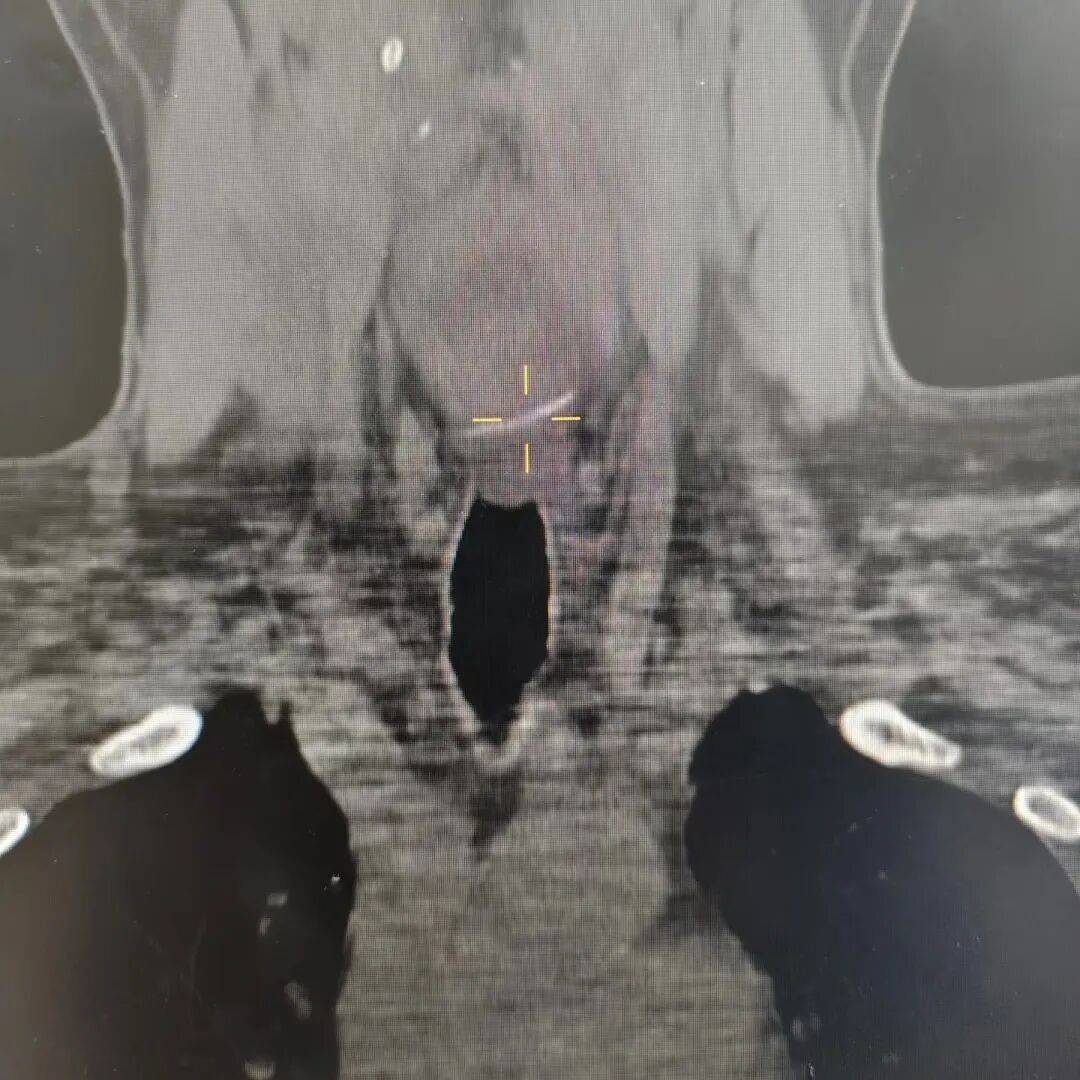

该院耳鼻喉科主任医师赵昊接诊后,立即为患者完善影像学检查,发现一根长约3厘米的鱼刺横向嵌顿在食管第一狭窄处,位置险要。食管第一狭窄毗邻重要血管与器官,鱼刺已刺破黏膜,若延误取出,极易引发食管穿孔、纵膈感染,甚至刺破大血管导致致命性大出血,情况十分危急。